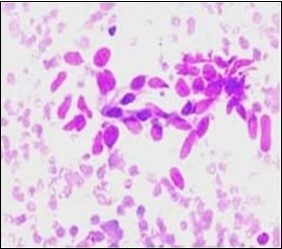

On gross examination, a tan coloured, gritty nodule, confined to the sternocleidomastoid muscle is delineated. Characteristically, smears obtained by fine needle aspiration cytology are composed of bland appearing, plump or normal fibroblasts and proliferating fibroblasts with an admixture of degenerative, atrophic skeletal muscle cells, giant myocytes with several nuclei, scattered, bare, bland nuclei or cells with fragmented, wispy cytoplasm and parallel aggregates of fibroblasts. The background is clear and devoid of cellular or nuclear debris. Sheets of spindle-shaped fibroblasts, atrophic muscle fibres and regenerating, multinucleated muscle giant cells are intermingled with the fibroblastic component 5, 6.

Figure 4.Fine needle aspiration cytology of fibromatosis colli delineating aggregates of plump, spindle-shaped cells admixed with fibroblasts, fibro-connective tissue fragments and intermingled red cell extravasation 11

Fine needle aspiration                cytology of fibromatosis colli delineating                   aggregates of plump, spindle-shaped cells admixed with fibroblasts, fibro-connective tissue fragments and intermingled red cell extravasation 11